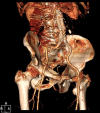

For high-risk patients, endovascular aortic aneurysm repair (EVAR) is a good option but may lead to serious complications, which should be addressed immediately. A 75-year-old man with a history of abdominal surgery underwent EVAR for an aneurysm of the abdominal aorta and iliac arteries. During EVAR, iliac artery rupture and graft limb occlusion occurred, and they were successfully managed by the additional deployment of an iliac stent graft and balloon thrombectomy, respectively. We, herein, report a rare case of the simultaneous development of the two fatal complications treated by the endovascular technique.